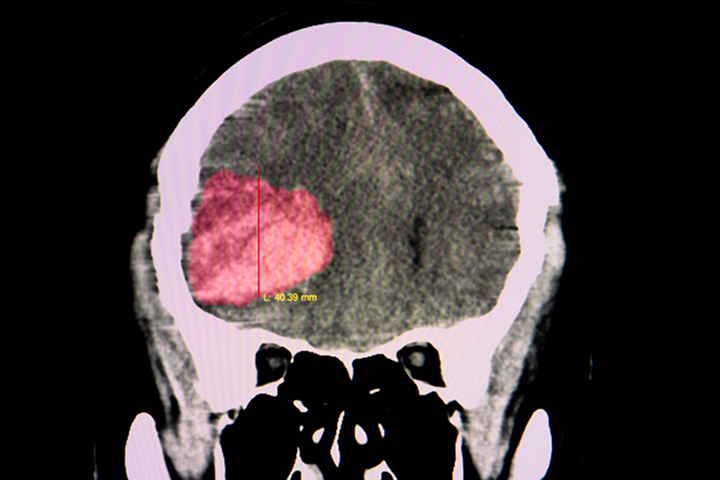

Lancet, 22 de mayo de 2019 Estos resultados excluyen todo, excepto un aumento muy modesto en el riesgo de hemorragia intracerebral recurrente con terapia antiplaquetaria en pacientes en terapia antitrombótica para la prevención de la enfermedad vascular oclusiva cuando desarrollaron hemorragia intracerebral. El riesgo de hemorragia intracerebral recurrente es probablemente demasiado pequeño para exceder los beneficios establecidos de la terapia antiplaquetaria para la prevención secundaria.